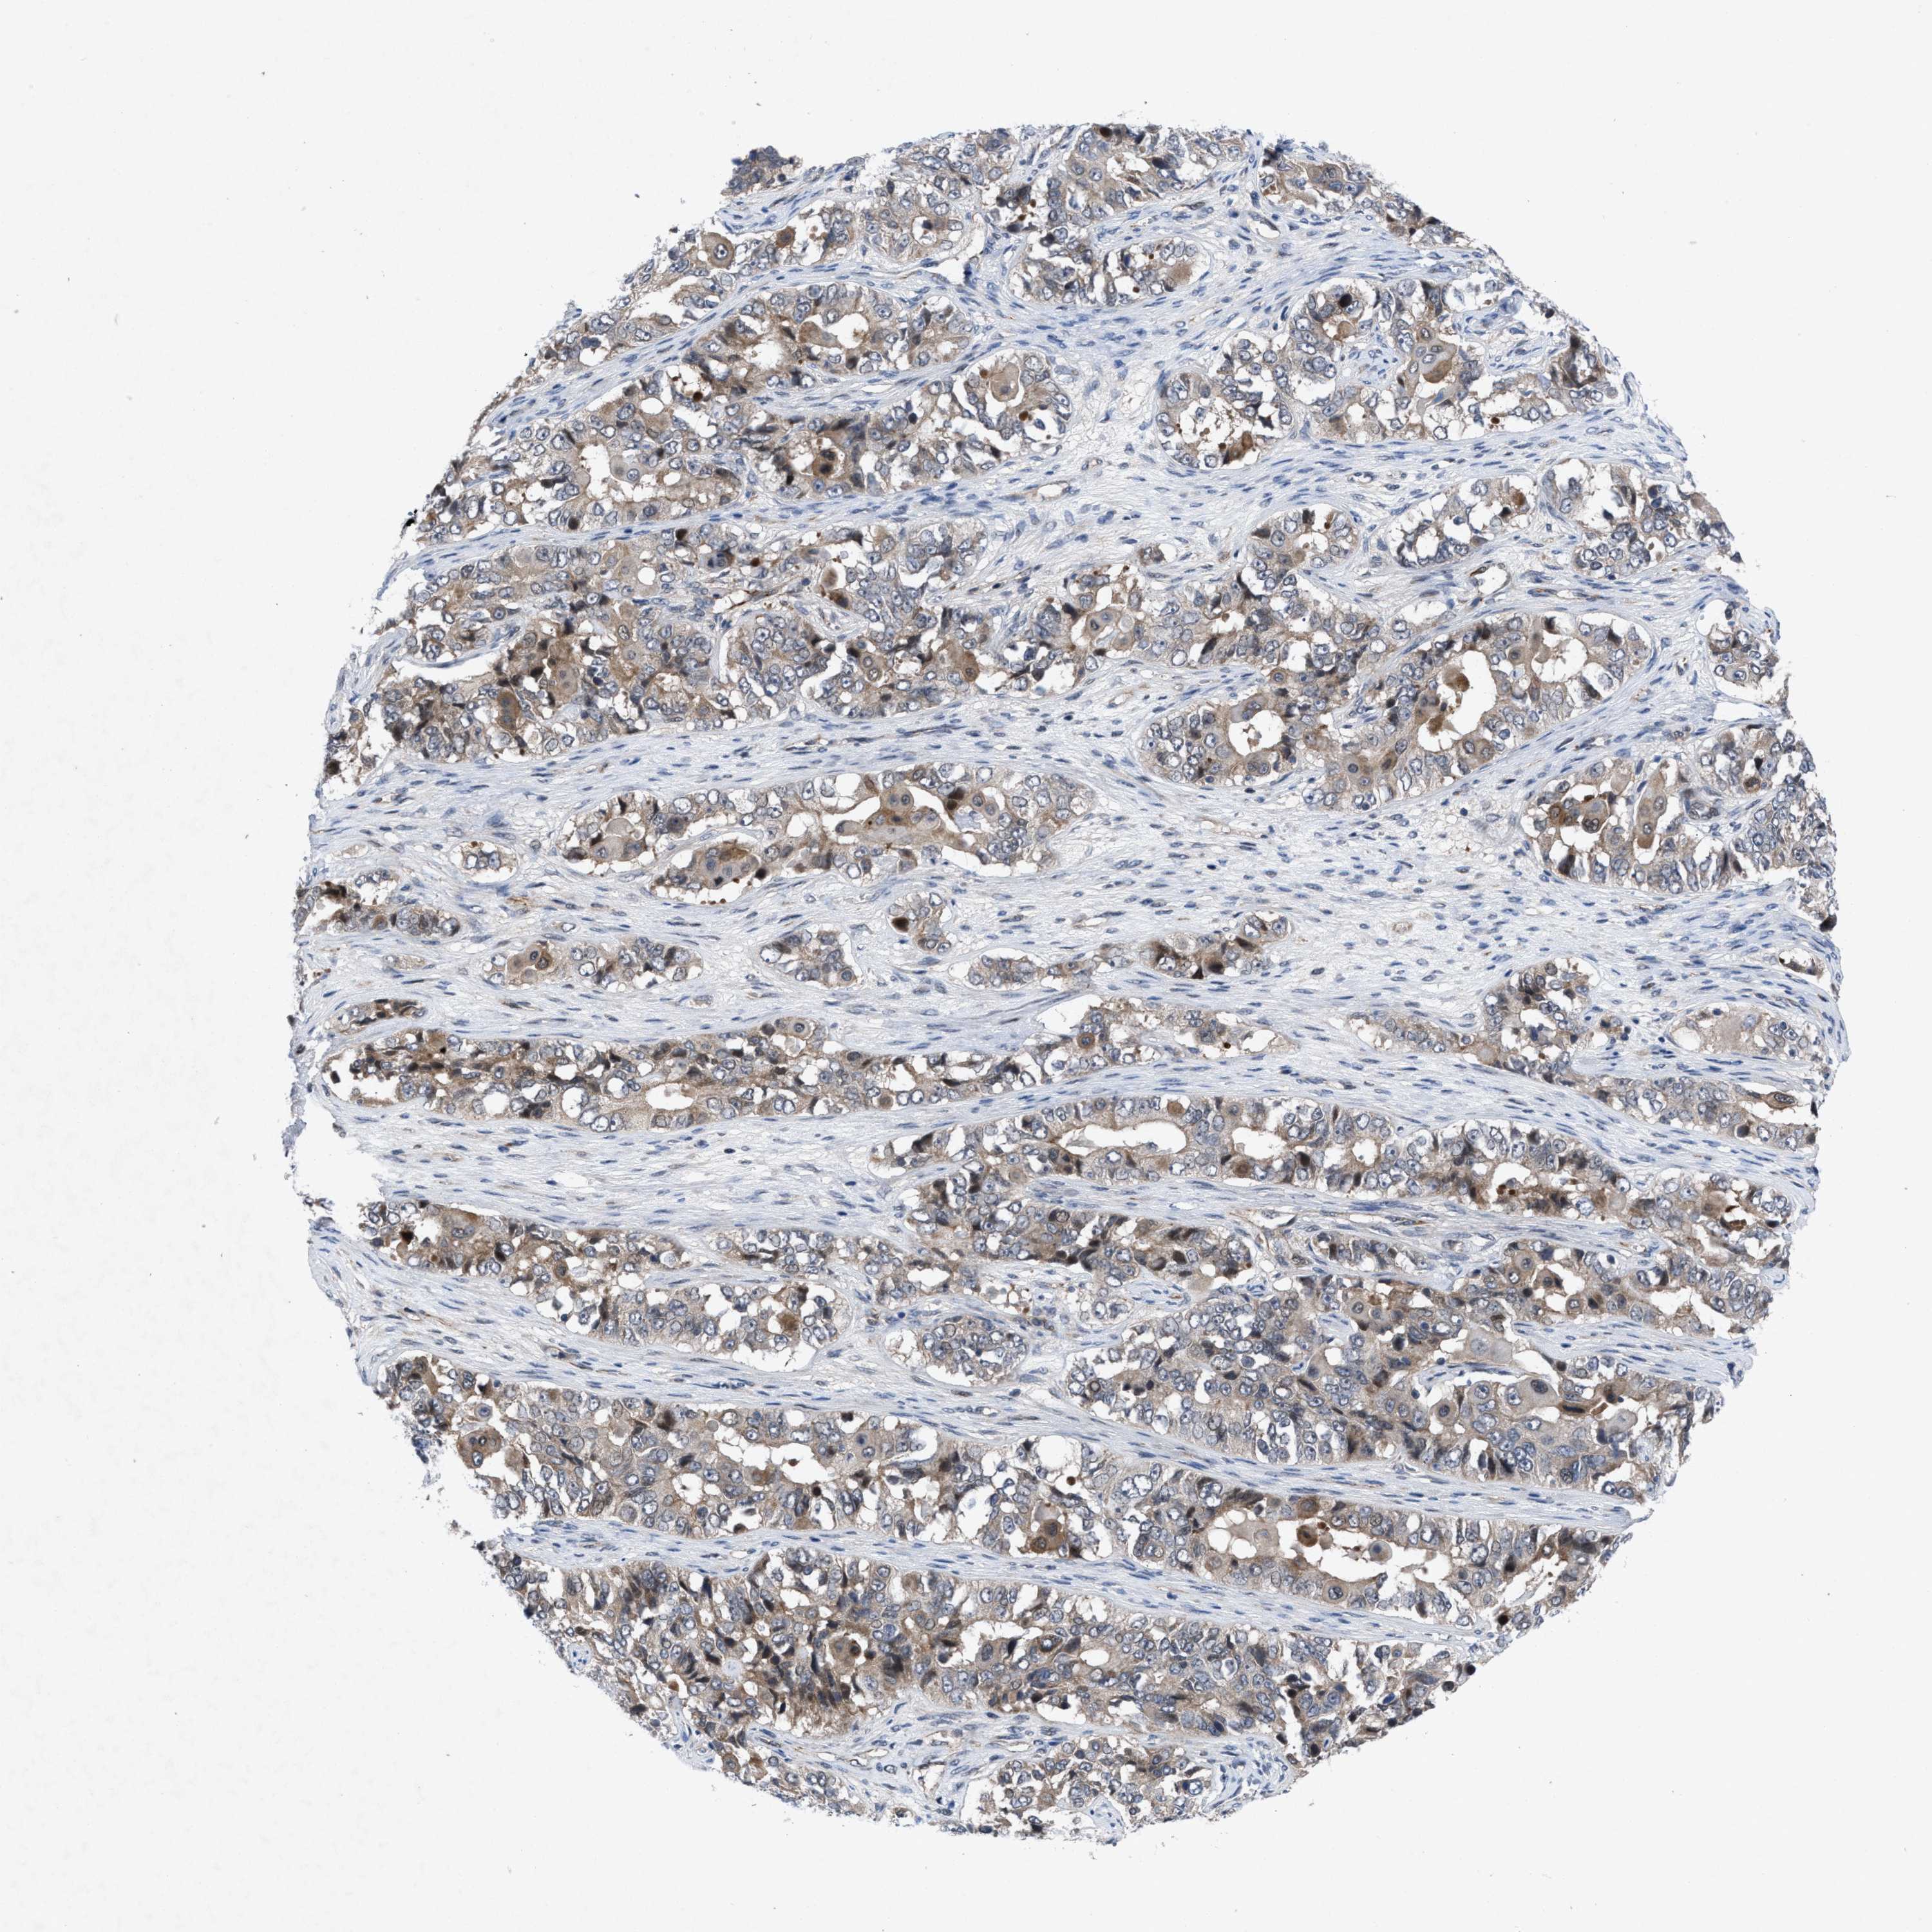

OVARIAN CANCER - Protein expressioni

A mouse-over function shows sample information and annotation data. Click on an image to view it in a full screen mode. Samples can be filtered based on level of antibody staining by selecting one or several of the following categories: high, medium, low and not detected. The assay and annotation is described here.

Note that samples used for immunohistochemistry by the Human Protein Atlas do not correspond to samples in the TCGA dataset.

Antibody stainingi

Antibody staining in the annotated cell types in the current human tissue is reported as not detected, low, medium, or high, based on conventional immunohistochemistry profiling in selected tissues. This score is based on the combination of the staining intensity and fraction of stained cells.

Each image is clickable and will lead to virtual microscopy that enables deeper exploration of all samples and also displays staining intensity scores, fraction scores and subcellular localization as well as patient and tissue information for each sample.

Antibody HPA019011

Staining

High

Medium

Low

Not detected

Intensity

Strong

Moderate

Weak

Negative

Quantity

>75%

75%-25%

<25%

None

Location

Nuclear

Cytoplasmic/membranous

Cytoplasmic/membranous,nuclear

Cystadenocarcinoma, serous, NOS

Carcinoma, endometroid

Cystadenocarcinoma, mucinous, NOS

Carcinoma, NOS